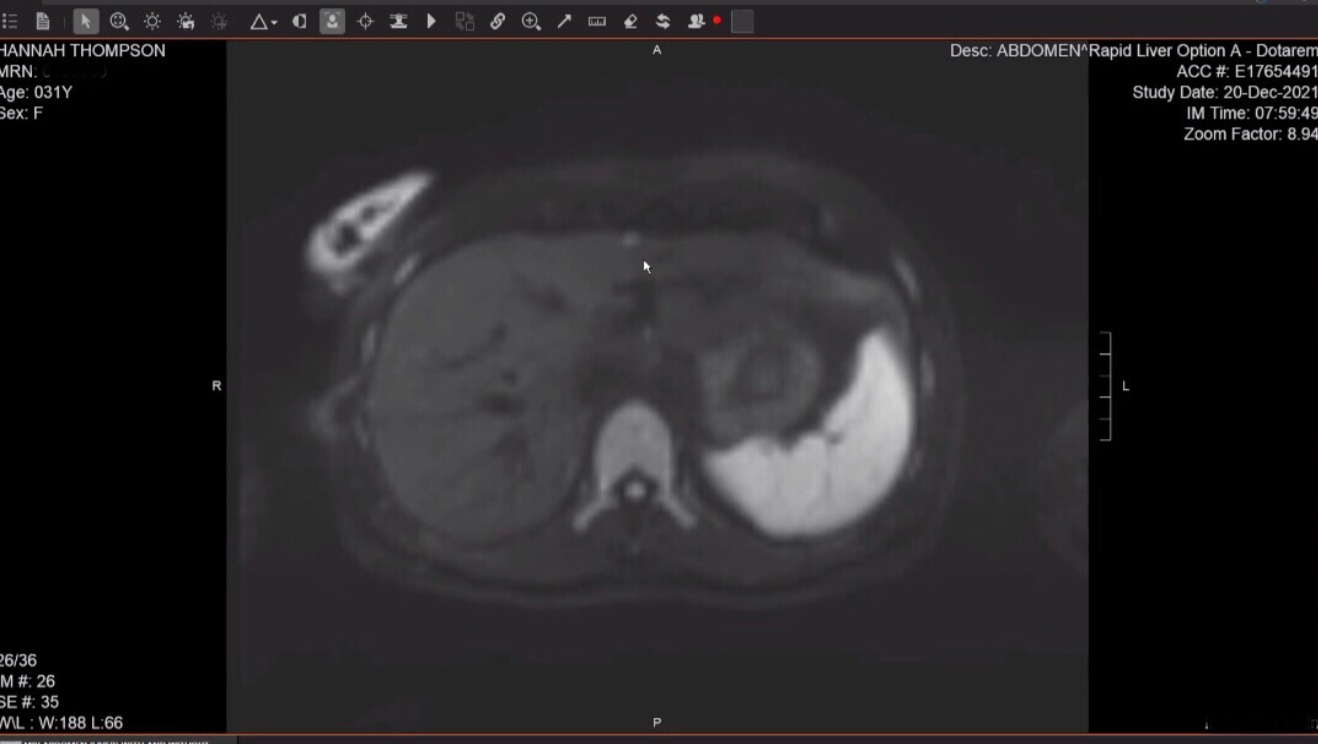

In March of 2021 I gave birth to a healthy baby boy we named Everett. The nights were long and the days longer, but we found a rhythm and the sleep started coming more regularly. In July of 2021 my eye checkup was fantastic. In December I got my body scans and in follow up with my oncologist to read the results, was told there was a spot on my liver that was suspicious. We made plans to consult with a surgeon, as the spot was small and anterior, so getting to it through surgery seemed feasible.

In February of 2022 my husband and I flew with Everett to MA for the laparoscopic surgery. The surgeon was great and came in after the procedure and let me know he removed the spot with clean margins. Initial testing on it was inconclusive, so they sent it off for an official biopsy.

On February 9th (our 3rd wedding anniversary), I made the mistake of checking my patient portal rather than waiting for the dr follow up the next day. The pathology report was in my profile and I read it. The spot on my liver was confirmed metastasis of my uveal melanoma. This automatically put me at stage 4 and ruined any chance we had of a happy anniversary celebration. The next day we met with the oncologist and he walked us through his recommendations. I would get a blood test to see if I was a match for a newly approved FDA drug, Tedtebentafusp